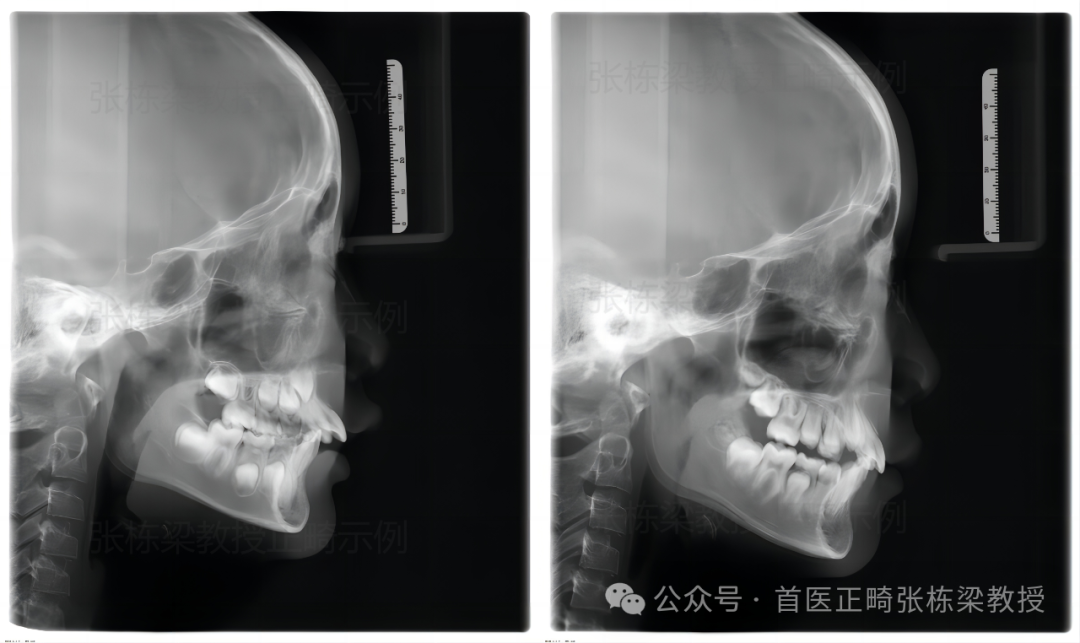

像这位9岁小朋友嘴凸、下巴后缩早期矫正改善效果也是不错的。

孩子存在的问题:骨性II类牙性 II 类 1 分类,下颌后缩,上前牙严重唇倾,深覆合,极度深覆盖,上牙弓狭窄。

早期矫正方案:上颌垫固定扩弓器,慢速扩弓,佩戴一个月后,当孩子上颌牙弓宽度到位后,后牙覆合覆盖充分后,就拆掉扩弓器。辅助生物调节器,让孩子弹舌训练每日 500 次,辅助维持上颌牙弓宽度。

后续增加佩戴口外弓,每天至少 12 小时,为期半年多时间,孩子下颌位置稳定,下颌生长发育限制解除,潜力释放,停戴矫治器,定期复诊,监测孩子后续生长发育。